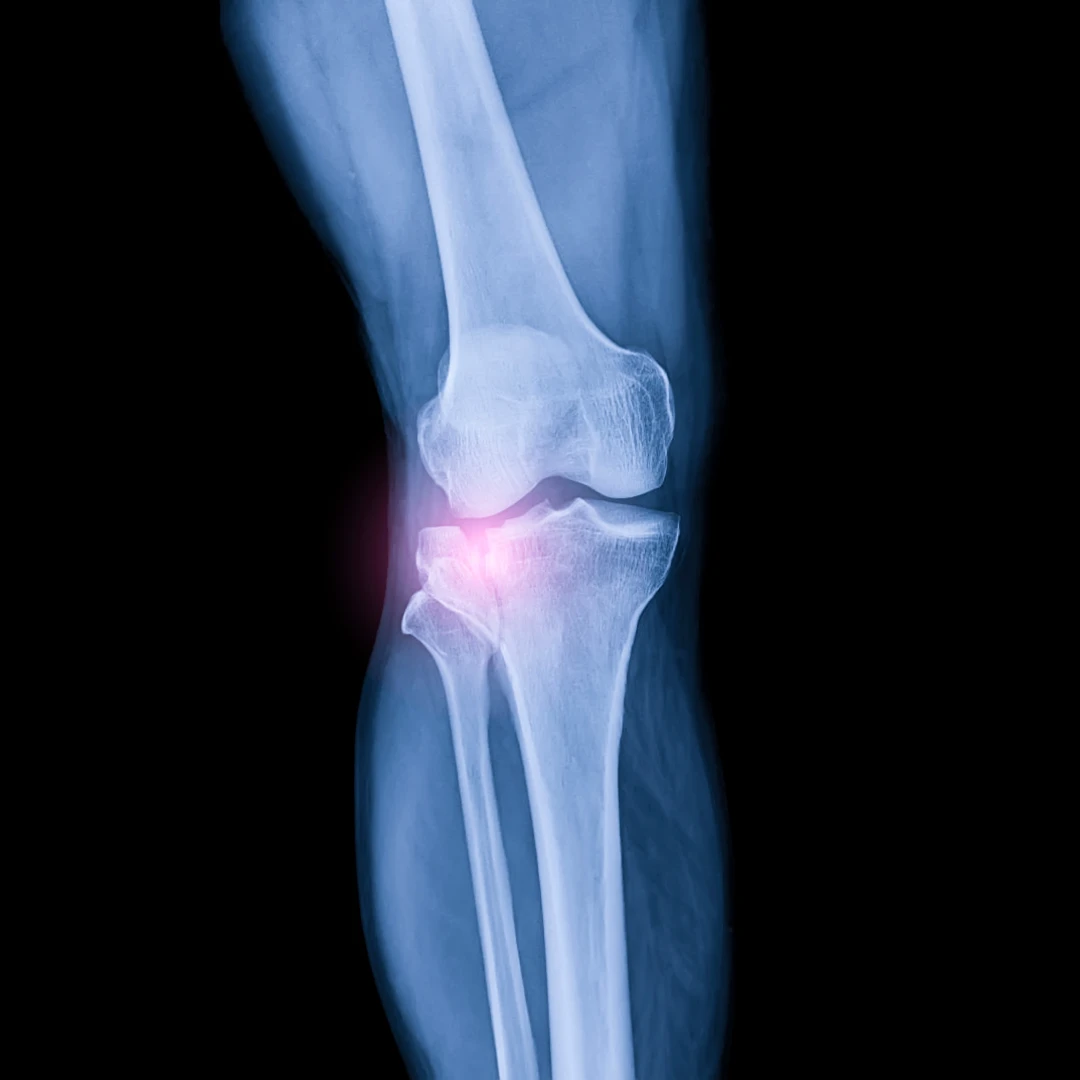

X-rays are a common medical imaging tool used to visualise the body's anatomy beneath the skin – this includes visualising the bones, internal soft tissues, and organs. X-rays are immensely useful in diagnosing and ruling out bone fractures, joint dislocations, and soft tissue injuries and are safe, cost-effective, and clinically effective in evaluating a person’s health.

X-ray uses electromagnetic energy beams that are invisible and intangible to create body images when the beams pass the human body. Due to the difference in density of the bones and internal organ soft tissue of the body, the electromagnetic ray that passes the affected area will produce various shards of grey on the film for the clinician to interpret.

Generally, higher-density objects such as bones, metals, and stones can appear whiter and brighter, while soft tissues and less dense objects will be darker in the X-ray images.

X-rays can be performed on various parts of the body. This makes X-rays unique, versatile, quick, and effective in assisting the physician to reach the correct diagnosis.

Bone/joint X-ray: effective in visualising the bone and joint structures of the upper and lower limbs. It is the main medical modality to diagnose bone fractures and joint dislocations.